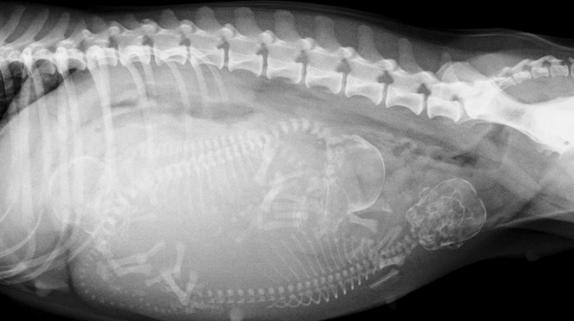

有经验的兽医通过轻轻触摸猫咪的腹部可以在怀孕17-25天时摸到怀孕后子宫内出现的孕囊。但更精确的判断就需要拍摄X线片及做B超检查了哦。

约在怀孕43-45天后拍摄X线片可以明显的看到小猫的骨骼~(请放心这时的X线片是不会对怀孕猫咪及小猫导致伤害的)。而约20天时,通过B超检查探测到的小猫心脏的跳动也是它们在告诉你“我很好~!请不要担心我!”